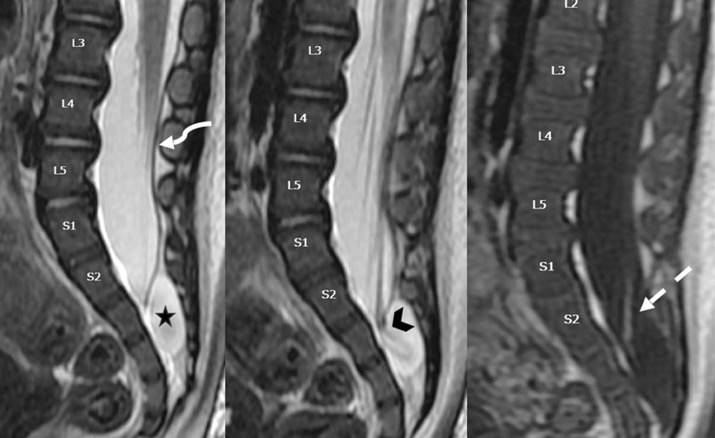

c. Lipomatose encéphalocraniocutanée (ECCL): peau, yeux, SNC)

ECCL: